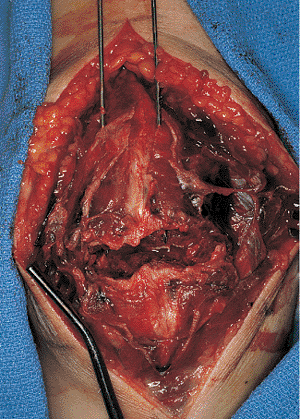

tissue and the prepatellar bursa. A hematoma is usually encountered as

soon as the bursa is opened, and it usually leads directly into the

fracture site (Fig. 24.3). Care should be taken

to minimize direct dissection of the fracture fragments. The soft

tissues surrounding the patella often hold nondisplaced fractures in

place, and if these are disrupted, the fragments may displace, creating

a more complicated and unstable fracture pattern. The major fracture

fragments should be exposed. Clot

should

be removed with a combination of small curettes and the use of a small

suction-tip device. Irrigation should be used liberally to help remove

the hematoma and small inconsequential comminuted fragments. The extent

of the medial and lateral retinacular injuries should be identified and

the edges tagged for later repair. The undersurface of the patella, in

addition to the patellofemoral groove, should be inspected for evidence

of articular damage. The knee joint should be inspected and irrigated

to remove any loose fragments.

![]() |

|

Figure 24.3.

Surgical exposure through a vertical midline incision showing the transverse fracture of the patella with medial and lateral retinaculum tears. The soft tissues have been left intact over the surfaces of the patella. |